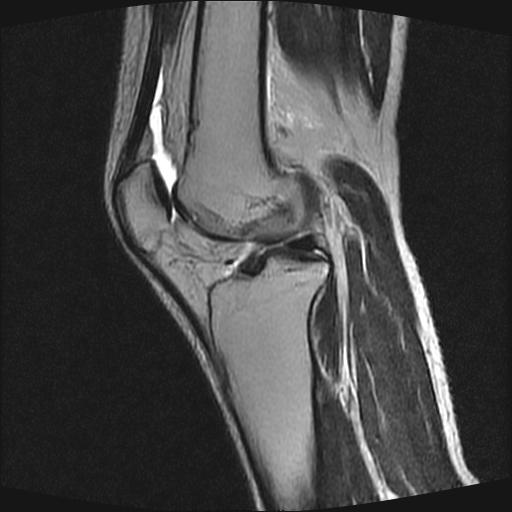

40岁男性,右膝关节外伤,x光平片示,髁间隆突撕脱骨折。

1、前交叉韧带撕裂;

2、外侧半月板后角撕裂;

3、关节腔积液。

前交叉韧带撕裂,关节腔积液.

半月板1-2级损伤   前交叉韧带撕裂伤   关节腔少量积液  诸骨未见新鲜外伤性改变

髁间隆突撕脱骨折;内侧副韧带损伤。

内侧副韧带撕裂及关节腔积液是肯定的,但是前交叉撕裂确定吗?会不会有容积效应的因素,因为前一张前交叉显示清楚,连续性良好,且较光滑。请问楼主有关节镜支持吗?我们医院也经常有这样的患者,但苦于没有关节镜,而无法对照、证实(除非完全断裂),出现了不同的诊断结果只能毫无意义的争论。

1、前交叉韧、内侧副韧带撕裂;

3、关节腔积液。4、髁间脊撕脱骨折。

除了关节积液外并无韧带撕裂,acl胫侧附着点有2束,正常情况下脂肪信号。此病例应加做压脂像以便观察是否有骨损伤。